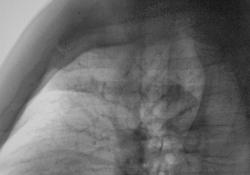

Мужчина средних лет полуатлетического сложения, жалоб не предъявляет, без вредных привычек.

Нет не ломал, травмы не было, не было ничего, вот это смутило, и заставило выставить изображения на сайт.

Надо бы допросить с пристрастием... У меня пока варианты:старый перелом и следствие синдрома Титце. Согласна, снатяжкой, не все укладывается...

Уже допрошен, и с пристрастием. Мужчина серьёзный, даже "рафинированный". О своём здоровье заботится не на словах.

Поддерживаю версию консолидированного перелома - может и не помнить, запросто!

Или - вариант аномалии (редкой, наверное! ), во всяком случае (по Т-граммам) в сторону негатива НЕ склоняюсь...

ГКО.